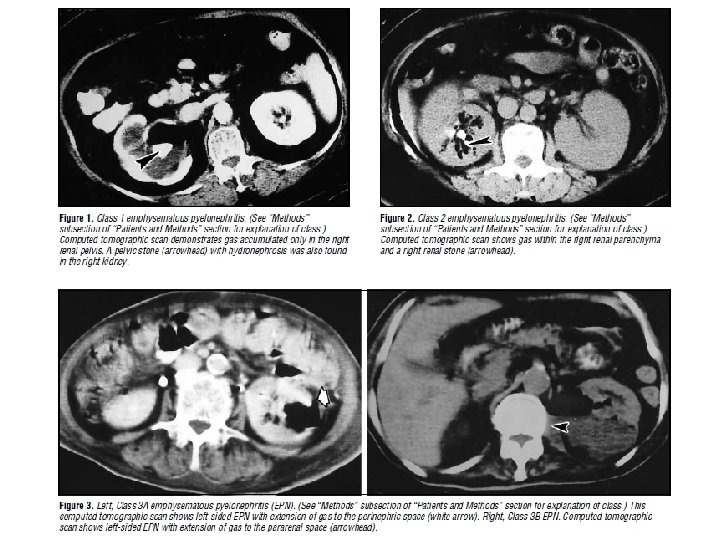

Prognostic classification Class 1: Gas in the collecting system only Class 2: Gas in the renal parenchyma without extension to the extrarenal space Class 3 A: Extension of gas or abscess to the perinephric space, between the fibrous renal capsule and the renal fascia Class 3 B: Extension of gas or abscess to the pararenal space, space beyond the renal fascia and/or extension to adjacent tissue Class 4: Bilateral emphysematous pyelonephritis or solitary functioning kidney with emphysematous pyelonephritis Arch Intern Med 2000 Mar 27; 160(6): 797 -805.

Arch Intern Med 2000 Mar 27; 160(6): 797 -805.